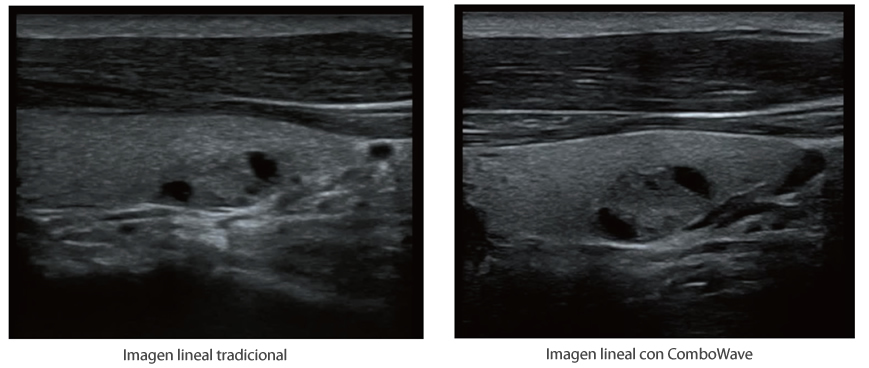

X-Insight es la soluci├│n intuitiva para una mejor visualizaci├│n.

Bas├Īndose en una profunda comprensi├│n de las necesidades del usuario, el sistema de ultrasonidos DC-60 Exp con X-Insight est├Ī dise?ado para ofrecer una alta eficiencia con im├Īgenes de precisi├│n, la cual se ve potenciada por una claridad inmediata, una inteligencia excepcional y benefici├Īndose de una c├│moda experiencia.